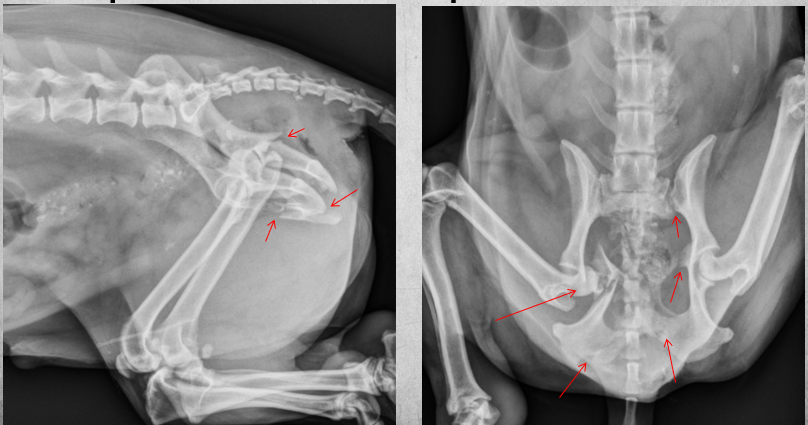

10

Q

2 years old male castrated cat

Severe sudden onset lameness of pelvic limb

A

Displaced capital physeal fracture of the left femoral head with mild cranial displacement of the femoral neck. On the frog-legged VD projections, this displacement is not visualizing so well.

Most of the physes of the pelvic limbs are at least partially open, including the intact right femoral capital physis (castrated young).

Diagnosis: Left sided capital physeal fracture of the left pelvic limb and delayed physeal closure in both hind limbs.